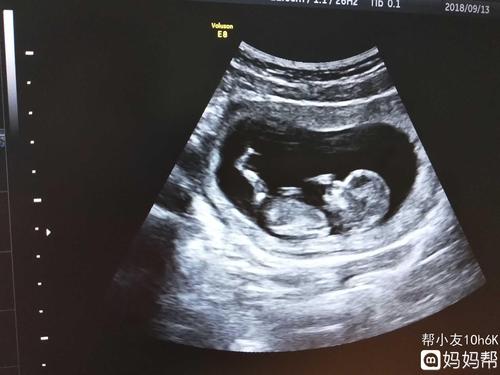

宝宝十二周nt 彩超

孕12周 ,nt检查看不到胎儿胳膊腿?

nt过啦,给你们欣赏一下照片吧!能看出男